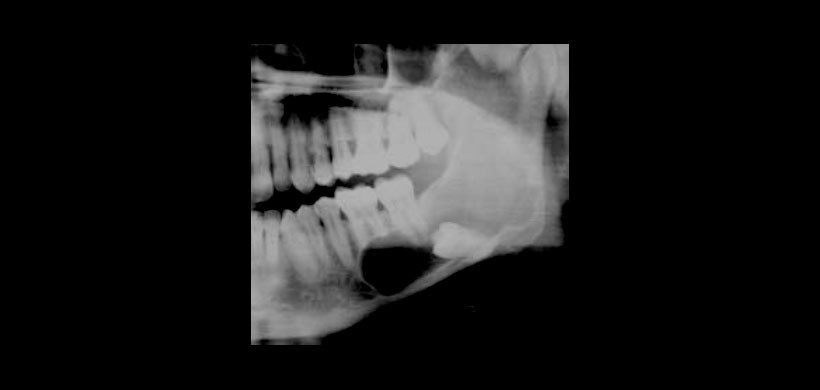

Radiográficamente, el 52% de las lesiones eran uniloculares y el 48% eran multiloculares; el 94,5% mostró bordes bien definidos. La información sobre la integridad de la cortical estaba disponible en sólo 24 casos: 50% mostró una perforación, un 8,3% erosión de las corticales y 8,3% adelgazamiento de estas mismas. (Fig 2) En cuanto a la reabsorción radicular se encontró en un 22% y en un 24% el desplazamiento de los dientes.(Fig 3)